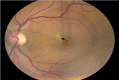

The authors report a case of a 46-year-old Hispanic male with central serous chorioretinopathy (CSC) following blunt trauma to the left eye. The patient presented with a complaint of throbbing headache and blurry vision in left eye. The patient was diagnosed with diabetes mellitus 1 year previous to the event. On examination, uncorrected visual acuity was 20/20 OD, 20/200 OS. No anisocoria or afferent pupillary defect was present. Intraocular pressure was normal. Subconjunctival haemorrhage and lid ecchymosis were present in OS and fundus examination showed serous macular detachment and central retinal pigment epithelium detachment, and no evidence of diabetic retinopathy. Optical coherence tomography OS showed subretinal fluid and fluorescein angiography demonstrated the typical 'smokestack' pattern of leakage into the subretinal space. The patient received observational therapy for 4 months and the CSC spontaneously resolved with visual acuity of 20/20 in left eye.